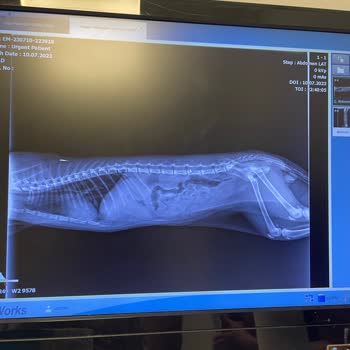

Prive veteriner, yavru kedime sırf para almak için yanlış teşhis koyup sağlığıyla oynadı. Genel muayene için götürdüğüm kedime sadece kilosuna bakıldı, karnı ve göğsü dinlendi. Ciğerler dolu denildi ve tırnakları kesilmiş olmasına rağmen tekrar kesildi. Sonrasında kan testi istediler ve yapıldı. Tes...